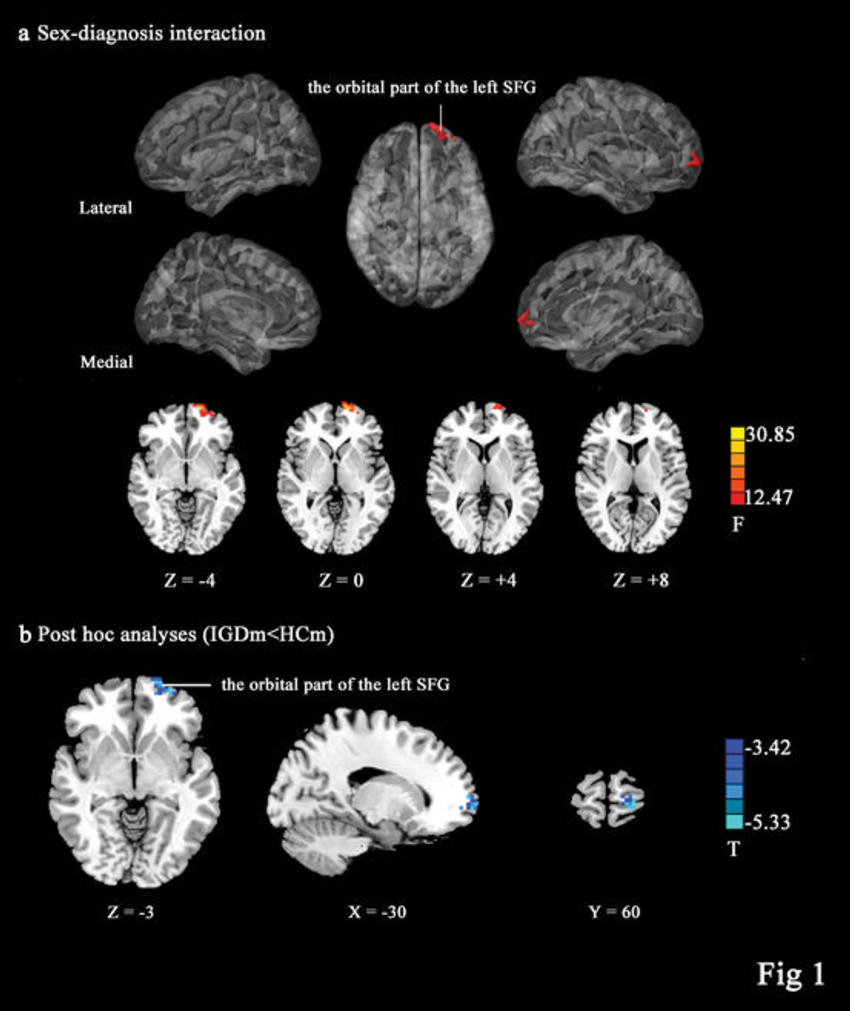

Figure 1. Images show amplitude of low-frequency fluctuation (ALFF) results. A: Images show brain regions with sex (Male, Female) and diagnosis (Internet Gaming Disorder, Health Control) interactions in the ALFF. B: When interaction effects occurred, post hoc pair-wise comparisons were performed within the interaction masks. Male participants with Internet Gaming Disorder showed lower ALFF values in the orbital part of the left superior frontal gyrus than male healthy controls.

The results illuminated key differences between the men and women with IGD. Men with IGD showed alterations in regional- and network-level brain function. In particular, they had lower brain activity in the superior frontal gyrus, an area of the brain's prefrontal lobe that is important to impulse control. The women with IGD did not exhibit any of these brain alterations.

"Our findings demonstrated that alterations in cerebral activity are observed in men with IGD, but not in women with IGD, and that the lower brain activity in the superior frontal gyrus in men with IGD may be associated with higher impulsivity," Dr. Sun said.